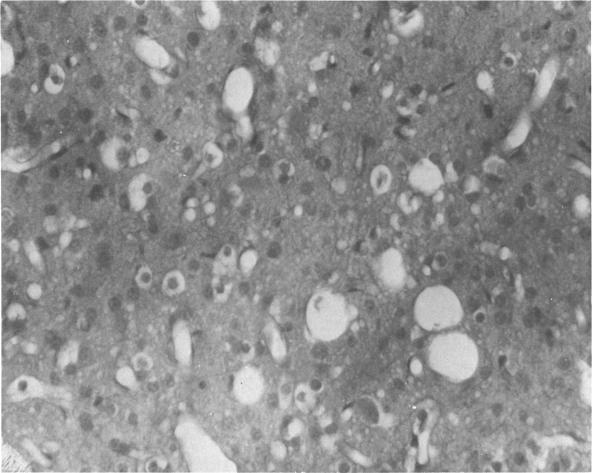

Lead subacetate (0.5g) and 1000 units of vitamin D were given three times a week to four newly-weaned rhesus monkeys. In addition, two animals received only the vitamin D. The poisoned animals had an increase in the urinary excretion of delta-aminolevulinic acid, an elevated content of lead in the blood, and a fall in hemoglobin concentration. Between 6 and 18 weeks the animals suddenly developed ataxia, nystagmus, generalized weakness, and convulsions. At this time the animals were killed by perfusion of fixative and the brain prepared for light and electron microscopic studies. Definite morphological evidence of disease was confined to the central nervous system, except for one animal which showed the characteristic renal inclusions of lead poisoning. All animals showed PAS-positive globules associated with blood vessels and an exudative edema involving the white matter of the cerebral hemispheres and cerebellum. Ultra-structurally, this appeared as a granular precipitate within an expanded extracellular space. Alterations of nerve fibers were not seen in the white matter but axonal swelling was observed in the cerebral cortex. The perikaryon and neuropil appeared normal. The control animals showed no significant cerebral changes.

给4只刚断奶的恒河猴每周3次注射0.5克碱式醋酸铅和1000单位维生素D。此外,2只动物只接受维生素D。中毒动物的δ-氨基乙酰丙酸尿排泄增加、血液中铅含量升高、血红蛋白浓度下降。在6至18周期间,动物突然出现共济失调、眼球震颤、全身无力和抽搐。此时,通过灌注固定剂处死动物,并准备大脑用于光镜和电镜研究。除一只动物显示出铅中毒特有的肾脏包涵体外,疾病的明确形态学证据仅限于中枢神经系统。所有动物均显示与血管相关的PAS阳性小球以及涉及大脑半球和小脑白质的渗出性水肿。在超微结构上,这表现为扩张的细胞外空间内的颗粒状沉淀。白质中未见神经纤维改变,但在大脑皮层观察到轴突肿胀。核周体和神经纤维网看起来正常。对照动物未显示明显的脑部变化。